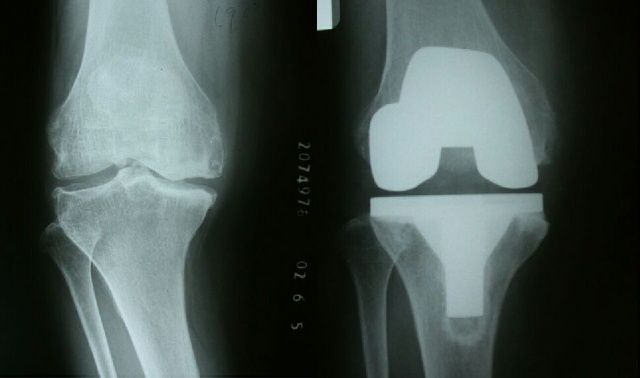

手術(shù)前后對(duì)照

術(shù)前術(shù)后對(duì)比照片,患者患者膝關(guān)節(jié)外翻畸形明顯矯正,活動(dòng)改善,疼痛緩解明顯。